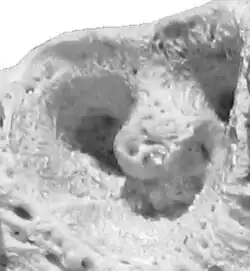

Na odontologia, um alvéolo dentário é a cavidade do osso da maxila e mandíbula onde se alojam os dentes.[1][2] O alvéolo existe em função dos dentes; na perda destes, o alvéolo deixa de existir.[3] Sua função principal é dar suporte aos dentes, para que possamos mastigar os alimentos. São cavidades nos maxilares nas quais as raízes dos dentes são mantidas no processo alveolar com o ligamento periodontal. O termo leigo para alvéolos dentais é cavidades dentárias. A articulação que conecta as raízes dos dentes e o alvéolo é chamada de gonfose (plural gomfoses). O osso alveolar é o osso que circunda as raízes dos dentes, formando cavidades ósseas.